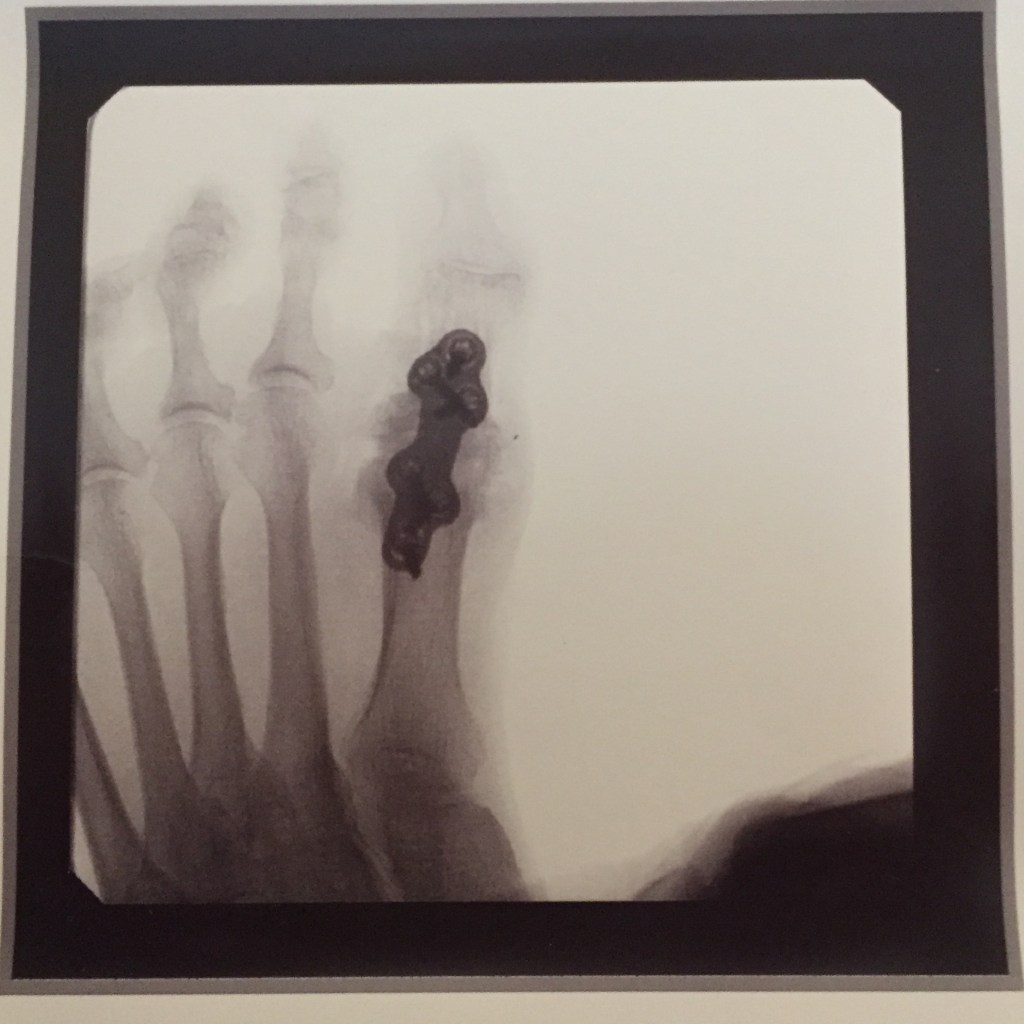

While recovering from this surgery, during a prayer time one morning, I was led again to a scene at the end of the book when Much-Afraid, a timid girl with crippled feet, was led to a ‘desolate altar in this valley of shadows’ to make a burnt offering as commanded by the Shepherd.’

So I have had to sit and wait for healing to come. I am still finding three months later that, no, the foot healing is not yet complete. I was reminded once again that healing, like transformation is a process. My will trips me more than my feet these days.